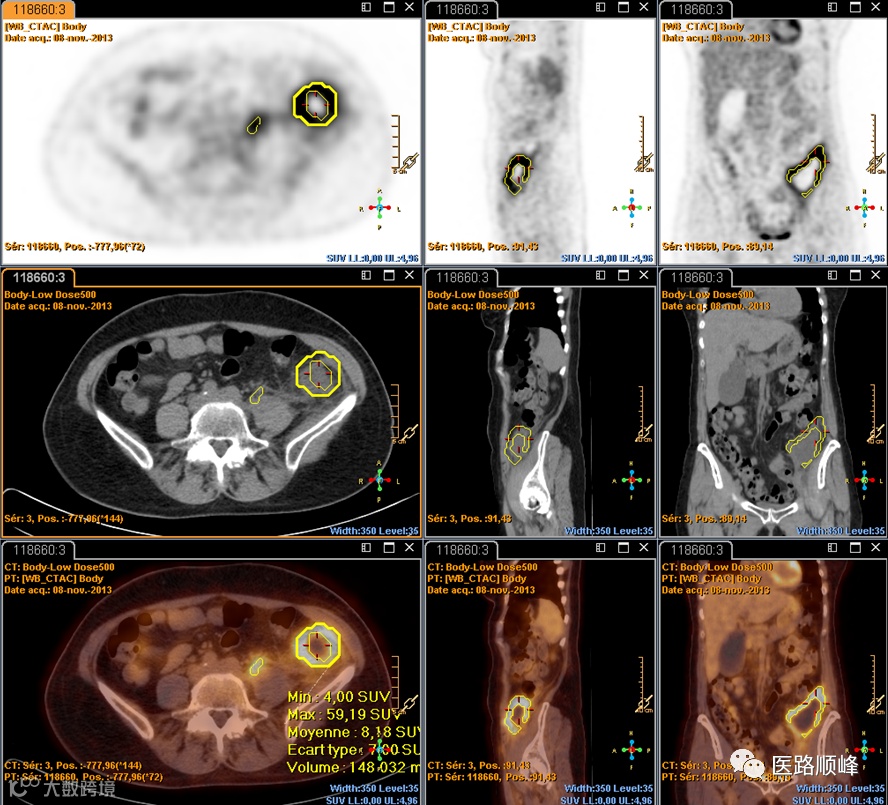

经过多年迭代,星云工作站已成为一个面向多病种、多模态、多类型设备的全面综合的影像后处理与分析平台。进入ISP时代以来,其功能不断增强,v12版本提供了支持CT、磁共振、PET、超声等模态,覆盖体检筛查、术前规划、术后随访等场景,面向心血管、神经、肿瘤等多种临床亚专科方向的超过100种应用功能。通过单个或多个模块的组合,完成从对患者的全面数据量化分析到三维重建、多模态融合等高级可视化显示,直通精准诊断的内核。